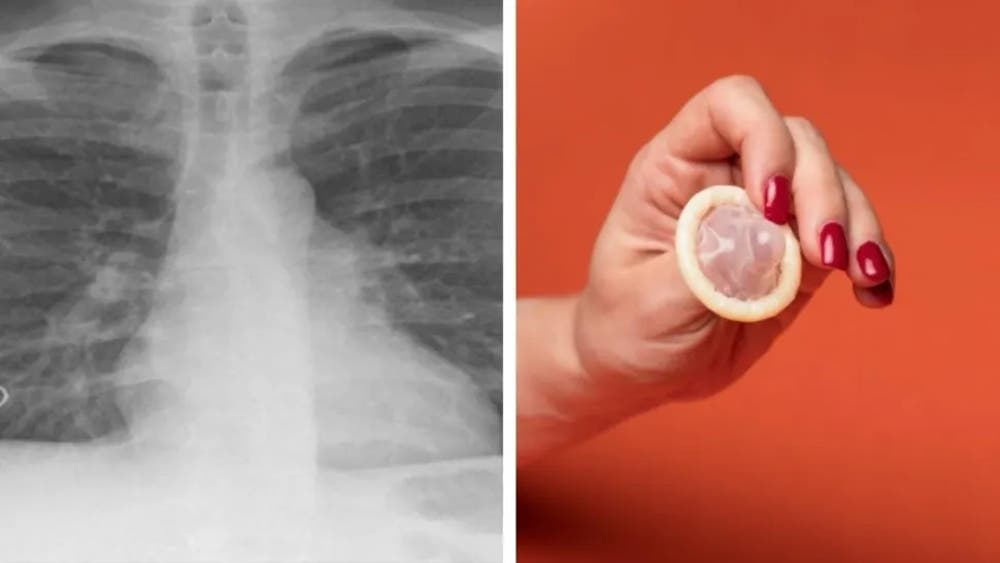

Una radiografía de su pecho reveló una lesión en el lóbulo superior derecho de sus pulmones, que parecía tener «una estructura en forma de bolsa invertida asentada en el bronquio», indicaron los especialistas, que tras una intervención quirúrgica extrajeron la misteriosa «bolsa».

Aunque la mayor parte de la misma fue destruida en todo el proceso, se comprobó que en realidad lo que provocó todo fue un preservativo.